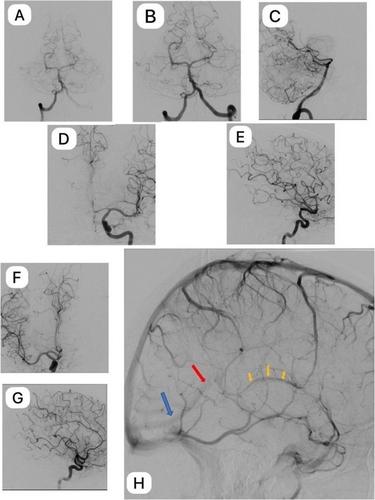

蛛网膜下腔出血的诊断是具有挑战性的,具有重要的临床,治疗和预后意义。延迟性NPMSAH(非动脉瘤性脑周SAH)可能包括细微的静脉损伤、静脉解剖异常或颅内静脉压升高。在所有“特发性”病例中,应考虑远端创伤性事件,并据此处理。

The diagnosis of a subarachnoid hemorrhage is challenging, and has important clinical, therapeutic and prognostic implications. Delayed NPMSAH (non-aneurysmal perimesencephalic SAH) may involve subtle venous injury, aberrant venous anatomy or increased intracranial venous pressure. In all “idiopathic” cases, a remote traumatic event should be considered, and approached accordingly.